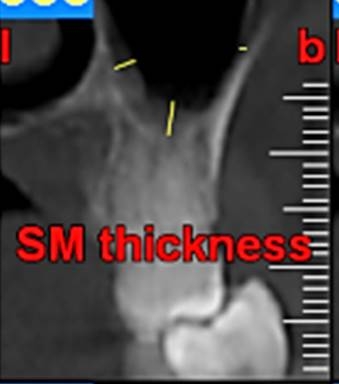

First, the radiographs were evaluated in relation to the endodontic and periodontal problems of the teeth and divided into 5 groups based on periapical index scoring, the periapical status was graded as follows: 1) normal periapical structures; 2) minor changes in bone structure; 3) some changes in bone structure with some loss of minerals; 4) periodontitis with a well-defined radiolucent area; and 5) severe periodontitis with exacerbating features.25 The patients’ genders were also recorded. In the next stage, the teeth were evaluated for the presence of periapical and periodontal lesions, followed by determination of the distance between the maxillary sinus floor and the nearest apex of the root of the first molar (Figure 1, A) and the nearest alveolar crest of the first molar on the buccal or lingual aspect (Figure 1, B). Furthermore, the buccopalatal thickness in the area superior to the apex of the first molar was determined in the coronal dimension (Figure 2). In the next stage, a line was drawn perpendicular to the line connecting the palatal crests of the first molars on both sides in order to measure the depth of the palate (Figure 3). Finally, the thickness of the schneiderian membrane was determined at three regions of the maxilla: medial, lateral and inferior. Then the mean of the 3 values was used as a reference (Figure 4).

Figure 4.the thickness of the schneiderian membrane